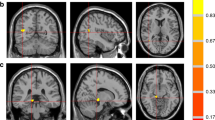

Anxiety scores showed negative associations with gray matter volumes (Fig. 2A) at the bilateral caudate (a, b), bilateral mid, left superior and right inferior frontal cortices, anterior, mid, posterior cingulate, putamen (g, h), hippocampus (e) and parahippocampus, anterior (c, d) and posterior insula (f), amygdala (i), pallidum, thalamus, basal forebrain, lingual gyrus, post and precentral cortices, inferior, mid, and superior occipital cortices, inferior, mid, and superior temporal cortices, superior parietal cortices, and prefrontal cortices in T2DM subjects. Negative relationships were observed in T2DM subjects between depression scores and gray matter volumes (Fig. 2B) at the amygdala (n), inferior frontal cortices, thalamus (o), anterior insula, hippocampus (j), para-hippocampal gyrus (m), prefrontal cortices (l), inferior, mid, and superior occipital cortices, and inferior, mid, superior (k) temporal cortices. Global MoCA values (cognition scores) showed positive correlations with gray matter volumes (Fig. 3) at the bilateral cerebellar cortices (k, l) and vermis, basal forebrain, anterior, and posterior (e, f) insula, pre- and post-central gyrus, middle and superior frontal cortices and prefrontal cortices (c), bilateral para-hippocampal gyrus, anterior (a, b), mid, and posterior (i) cingulate, hippocampus (d), amygdala (g, h), putamen, superior parietal gyrus, inferior, and mid occipital and inferior, mid, and superior temporal gyrus, and lingual gyrus (j). The correlation coefficients of gray matter volumes for all brain regions showing significant association with anxiety, depression, and cognitive scores are tabulated in Table 3.

Negative correlations emerged between gray matter volume and behavioral symptoms in T2DM subjects. Negative correlations appeared between gray matter volume and anxiety scores at the bilateral caudate (a,b), anterior (c,d), and posterior (f) insula, and hippocampus (e), bilateral putamen (g,h), amygdala (i) and with depression levels at right hippocampus (j), left superior temporal (k) and prefrontal (l) cortices, right parahippocampus (m), right amygdala (n), and left thalamus (o). Figure conventions are same as in Fig. 1.

Cognition showed positive associations with gray matter volume in T2DM subjects in several brain sites. Positive correlations appeared between gray matter volume and MoCA scores at the bilateral anterior (a,b) and right posterior (i) cingulate, prefrontal cortices (c), hippocampus (d), bilateral posterior insula (e,f), bilateral amygdala (g,h), and right lingual gyrus (j) and bilateral cerebellar cortices (k,l). Figure conventions are same as in Fig. 1.

The overlap between ANCOVA findings for gray matter volume between T2DM patients and control subjects and partial correlations between gray matter volumes and mood and cognitive symptoms in multiple specific brain regions that regulate cognition (hippocampus, prefrontal cortex, and cerebellum), anxiety (hippocampus, cingulate, insula, and amygdala), and depressive symptoms (hippocampus, cingulate, and insula) are shown in Fig. 4.

Significant clusters from ANCOVA (gray matter volumes; T2DM vs controls) and correlational analyses (gray matter volumes vs BAI, BDI-II, and MoCA scores; T2DM). Multiple sites that are involved in cognition (hippocampus, prefrontal cortex, parahippocampus, cingulate, insula, and cerebellum), anxiety (hippocampus, cingulate, insula, and amygdala), and depression (hippocampus, cingulate, and insula) regulation overlapped between group differences and correlation analyses that are marked with arrows.